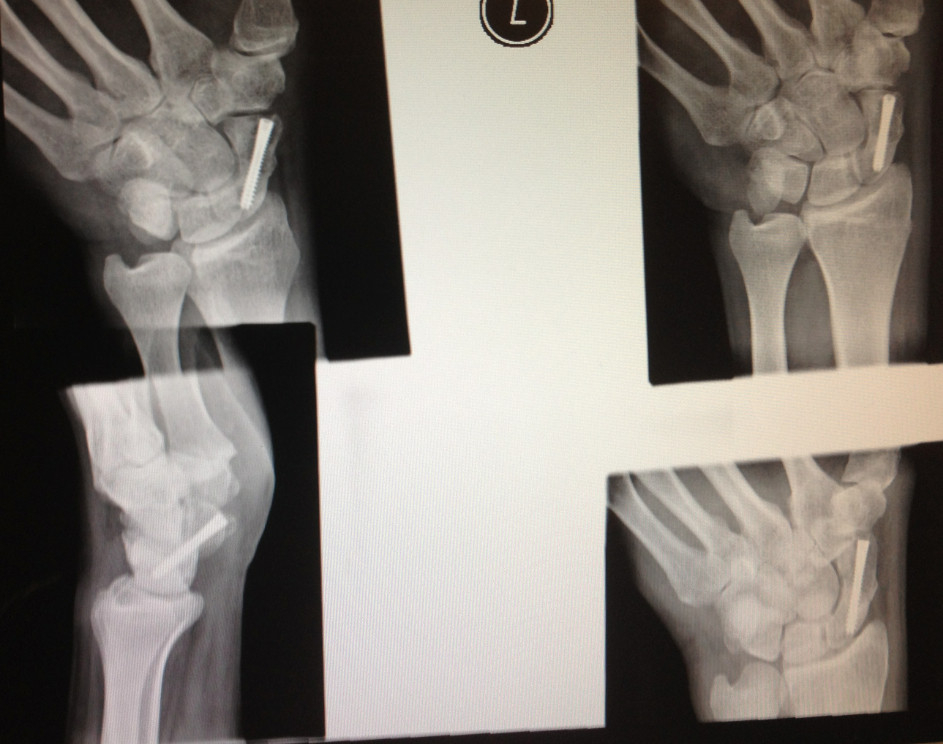

Well I'm glad you're ok and you've recovered

I can only imagine how debilitating it must have been for you with one hand in a cast unable to hold your iPhone and iTab in one hand and not being able to swipe with the other.